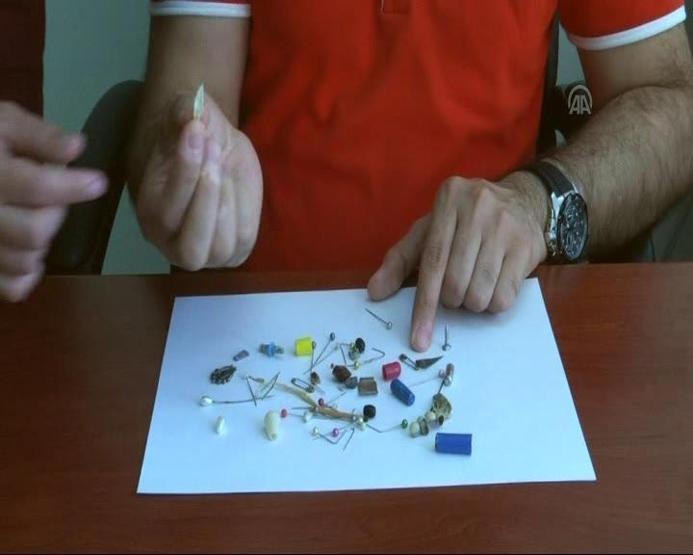

Cumhuriyet Üniversitesi (CÜ) Tıp Fakültesi Araştırma ve Uygulama Hastanesi Göğüs Cerrahisi Anabilim Dalı Servisi'nde insanların yanlışlıkla yuttuğu cisimlerden oluşturulan koleksiyon, görenleri hayrete düşürüyor. İğne, metal kolye, vida, protez diş, dikiş iğnesi, kemik parçası, pisi pisi otu, çivi ve akasya dikeni gibi bu cisimlerden koleksiyon yapan hekimler, vatandaşların ağızlarına aldıkları şeylere dikkat etmeleri ve herhangi bir cisim yutulması halinde vakit kaybetmeden hastaneye başvurması gerektiği konusunda uyarıyor.

Operasyonlarda çok tuhaf yabancı cisimlerle karşılaştıklarını ve şaşırdıklarını anlatan Şahin, "Çıkardığımız bu cisimlerin bir kısmını servisimizde biriktiriyoruz ve bir koleksiyon oluşturduk. Yıllardır çıkardıklarımız biriktirdiklerimizin 20-30 katı kadar" dedi.

Prof. Dr. Şahin, çıkardıkları cisimler arasında iğneler, metal kolyeler, vidalar, protez dişler, dikiş iğneleri, kemik parçaları, pisi pisi otları, çiviler ve akasya dikeni bulunduğunu kaydetti.

Yutulan cisimler arasında en çok iğne bulunduğunu dile getiren Prof. Dr. Ekber Şahin, fındık ve fıstık gibi çerezlerin de nefes borusuna kaçmasına sıklıkla rastladıklarını ifade etti.

İnsanların, midesinden ve nefes borusundan çıkan cisimleri anı olarak sakladıklarını söyleyen Şahin, "Hepsi olamasa da bir kısmını anı olarak saklıyoruz. Zaten organik olanları saklama şansımız yok. Her bir vakanın bizde ayrı ayrı anısı vardır. Her hastayı hatırlarız, hikayeleri farklı farklıdır. Böyle bir koleksiyon oluşturmaya devam ediyoruz" diye konuştu.